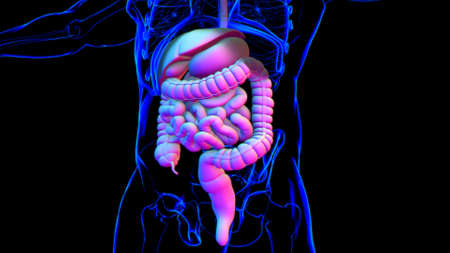

Human Digestive System Anatomy For Medical Concept 3D Illustration